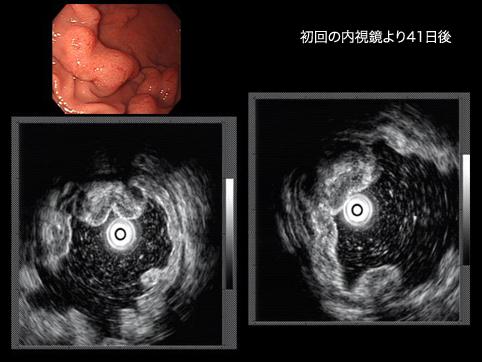

症例提示(所在地,施設名等): 佐賀県・ 佐賀大学医学部放射線科 (水口先生からの提供症例)

症例登録日 2009/09/24

画像数 29

性別 女性

年齢 70-74

疾患(病理主体)の分類炎症性・潰瘍性疾患/その他

部位(臓器別)胃(部位)/その他

検査方法エコー